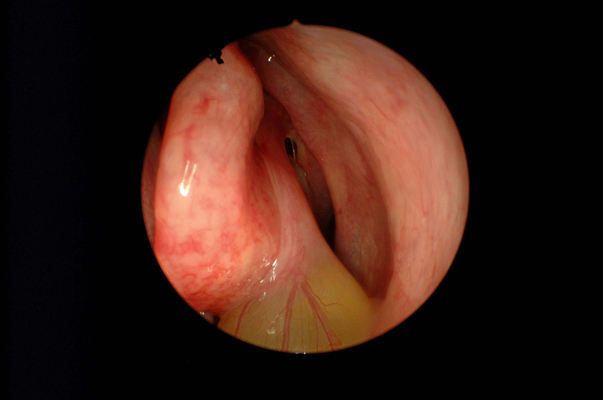

鼻竇炎圖片